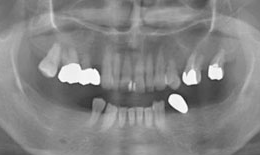

インプラント症例(9)女性 58歳

治療方法

- インプラントを6本埋め込んで、セラミックスクラウンを被せた

| インプラント |

フィクスチャー6本 |

285,000×6=1,710,000円(税抜) |

| 上部構造(ハイブリッドクラウン)7本 |

135,000×7=945,000円(税抜) |